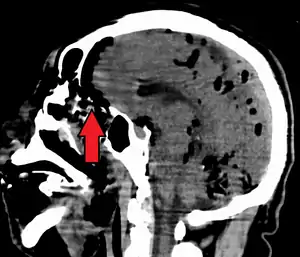

| Pneumocephalus and comminuted fracture of the frontal sinus |

CT scans of patients with a tension pneumocephalus typically show air that compresses the frontal lobes of the brain, which results in a tented appearance of the brain in the skull known as the Mount Fuji sign.[1][2][3] The name is derived from the resemblance of the brain to Mount Fuji in Japan, a volcano known for its symmetrical cone. In typical cases, there is a symmetrical depression near the midline (such as the crater of a volcano), due to intact bridging veins.[3] Its occurrence seems to be limited to tension pneumocephalus (not occurring in pneumocephalus without tension).[4] The sign was first described by a team of Japanese neurosurgeons.[5]